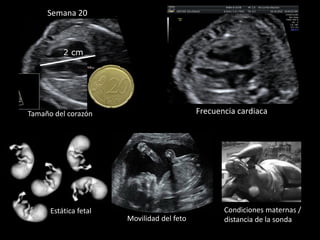

Frecuencia cardiaca

Estática fetal Condiciones maternas /

distancia de la sondaMovilidad del feto

2 cm

Semana 20

Tamaño del corazón